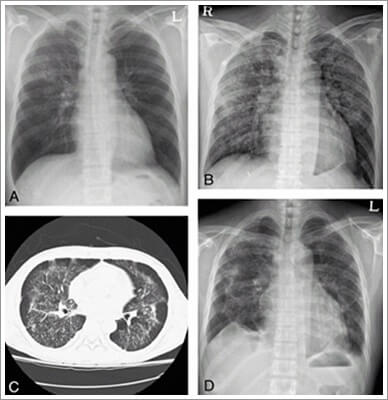

파라 인플루엔자 감염증의 진단을 위해서는 상기도 감염을 일으키는 바이러스 종류를 감별해야 한다. 기도 분비물 후두 면봉법, 비인두 세척액에서 바이러스를 발견하여 정확하게 진단한다. 바이러스는 세포 배양 검사나 유전자를 이용한 PCR 검사에서 확인할 수 있다.